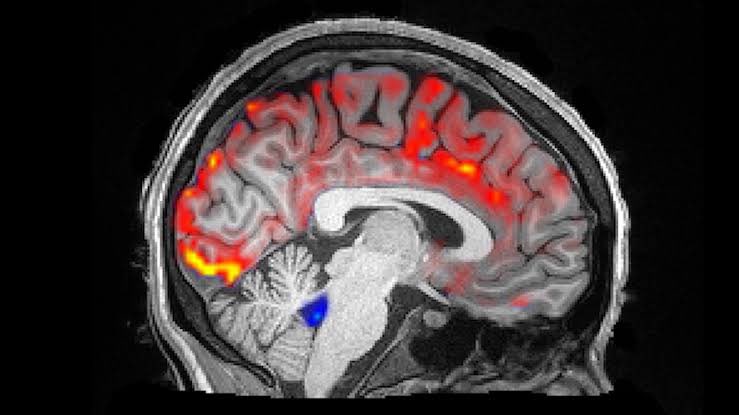

هذه أول صور تظهر للمجتمع العلمي على الإطلاق ، فعندما ننام ، تغسل موجات السائل النخاعي فوق الدماغ لإزالة (الأفكار السلبية).

بعد بضع ثوان ، سيتدفق الدم من رأسك. بعد ذلك ، سيتدفق سائل مائي يسمى السائل النخاعي (CSF) ، ويغسل عبر دماغك بموجات إيقاعية نابضة.